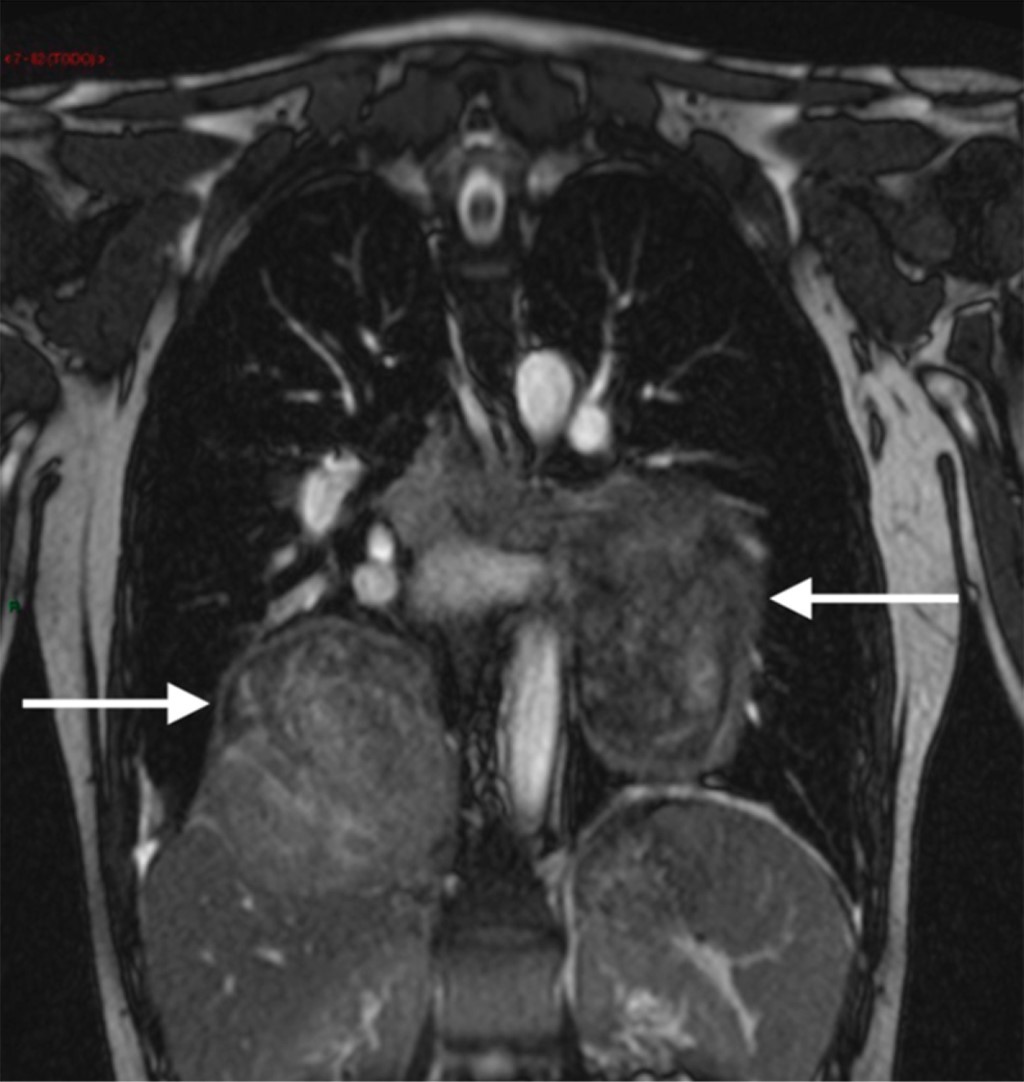

Surgical resection of oligometastasis of a monophasic synovial sarcoma in the lung

Synovial sarcoma is a rare, aggressive neoplasm resulting from mesenchymal stroma comprised of spindle cells with some epithelial differentiation. This condition accounts for 5%–10% of all soft-tissue sarcomas. Among synovial sarcomas, 50% metastasize. For patients with unresectable disease at diagnosis (Stage-IV), 5-year survival rates of 40% and 60% have been reported. We present a case of recurrent monophasic synovial sarcoma oligometastatic in which surgical resection was performed, reinforcing its impact on increased survival in Stage IV disease. Anatomopathological results based on immunohistochemistry indicate that this case arose from a previously known primary synovial sarcoma.

Figure 1